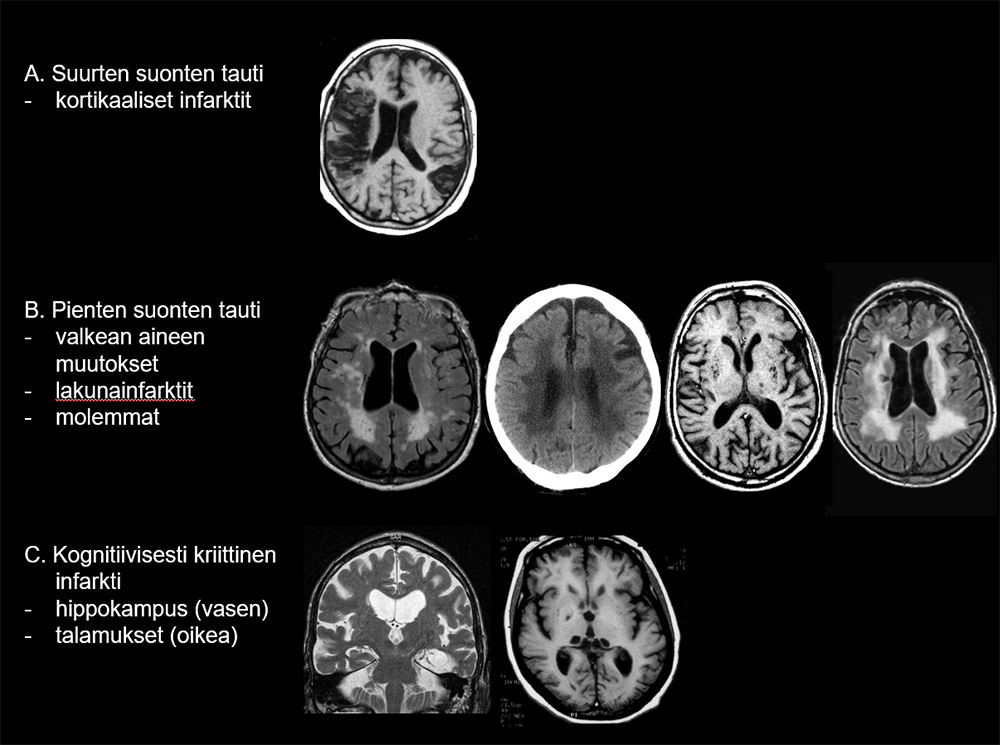

Vaskulaariseen kognitiiviseen heikentymään liittyvän aivoverenkiertosairauden päätyypit ja niitä kuvaavat aivojen magneetti- tai TT-kuvalöydökset

Suurten suonten taudissa (A) löydöstä hallitsevat yksi tai useampia kortikaalisia infarkteja.

Pienten suonten taudissa (B) nähtävät valkean aineen muutokset näkyvät MK:ssa herkimmin FLAIR-sekvenssissä. Keskivaikeat ja vaikea-asteiset valkean aineen muutokset näkyvät myös TT-tutkimuksessa. Lakunainfarktit näkyvät T1-3D-kuvissa, ja niihin voi liittyä FLAIR-sekvenssissä kirkassignaalinen reunus. Osalla potilaista on sekä valkean aineen muutoksia että lakunoita. Kognitiivisesti kriittisen alueen infarkti (C) voi sijaita esimerkiksi hippokampuksessa (vasen kuva) tai talamuksissa ja basaalitumakealueella (oikea kuva).

Kuvien lähde: Erkinjuntti T, Remes A, Rinne J, Soininen H. Muistisairaudet. Kustannus Oy Duodecim. 2015